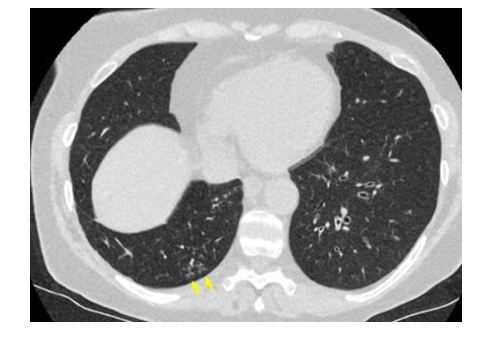

CO-RADS 2: Hình 2 – 3 – 4

Hình 2: Hình ảnh tổn thương CT: “Tree-in-bub sign” vùng ngoại vi phân thùy sau dưới bên phải, giãn & dầy nhẹ thành phế quản vùng trung tâm thùy dưới phổi trái. Không thấy tổn thương GGO. (Tổn thương giống viêm phế quản hơn COVID 19)

Hình 3: Hình ảnh tổn thương CT bao gồm giãn & dầy nhẹ thành phế quản, “tree-in-bub sign” & hình đông đặc. Không thấy tổn thương GGO.

Hình 4: Hình ảnh tổn thương CT bao gồm đông đặc thùy phổi & “tree-in-bub sign” (mũi tên). BN bị viêm phổi do nhiễm khuẩn lan tràn theo đường phế quản (dấu hiệu búp cây).